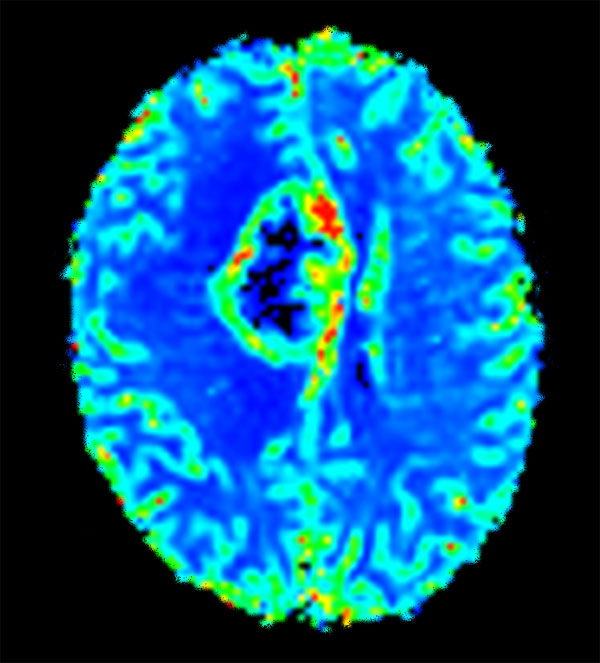

Advanced Neuro imaging - pCASL

Clinique Saint Joseph Imagerie Medicale, Liege, Belgium